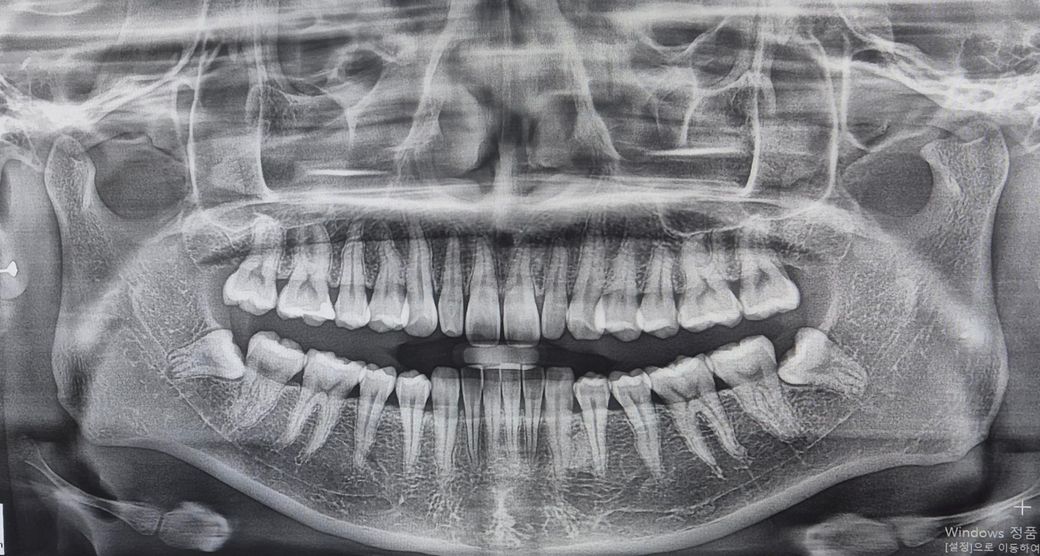

제 구강 엑스레이 사진인데 상태가 어떤지 봐주세요!

많이 안좋은 가요?ㅠㅠ

혹시 안좋다면 어디가 안좋은지 자세히 알려주세요!!

사진으로만 봤을 경우에는 큰 문제가 있어 보이진 않습니다. 왜곡되어 있는 사랑니또한 크게 문제를 발생시키지 않기 때문에 발치를 할 필요는 없을 것으로 생각됩니다.

제 구강 엑스레이 사진인데 상태가 어떤지 봐주세요! 많이 안좋은 가요?ㅠㅠ -> 정상입니다

엑스레이 상으로는 크게 문제가 없어 보입니다. 하지만 아래 사랑니는 작은 사진을 촬영해보시는게 좋을것같습니다.